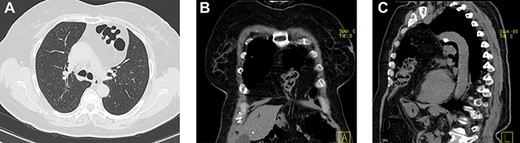

She had a chest X-ray done (Fig. 1) that showed widening of the mediastinum, as well as a few air-fluid levels, which raised suspicion of a diaphragmatic hernia. She also had a thoracic CT done (Fig. 2) that revealed a large hernia in the anterior mediastinum, containing transverse colon and a significant amount of ‘omentum,’ causing right side heart deviation.

(a–c) Axial, coronal and sagittal images, respectively, of thoracic and abdominal CT showing the localization of this hernia.